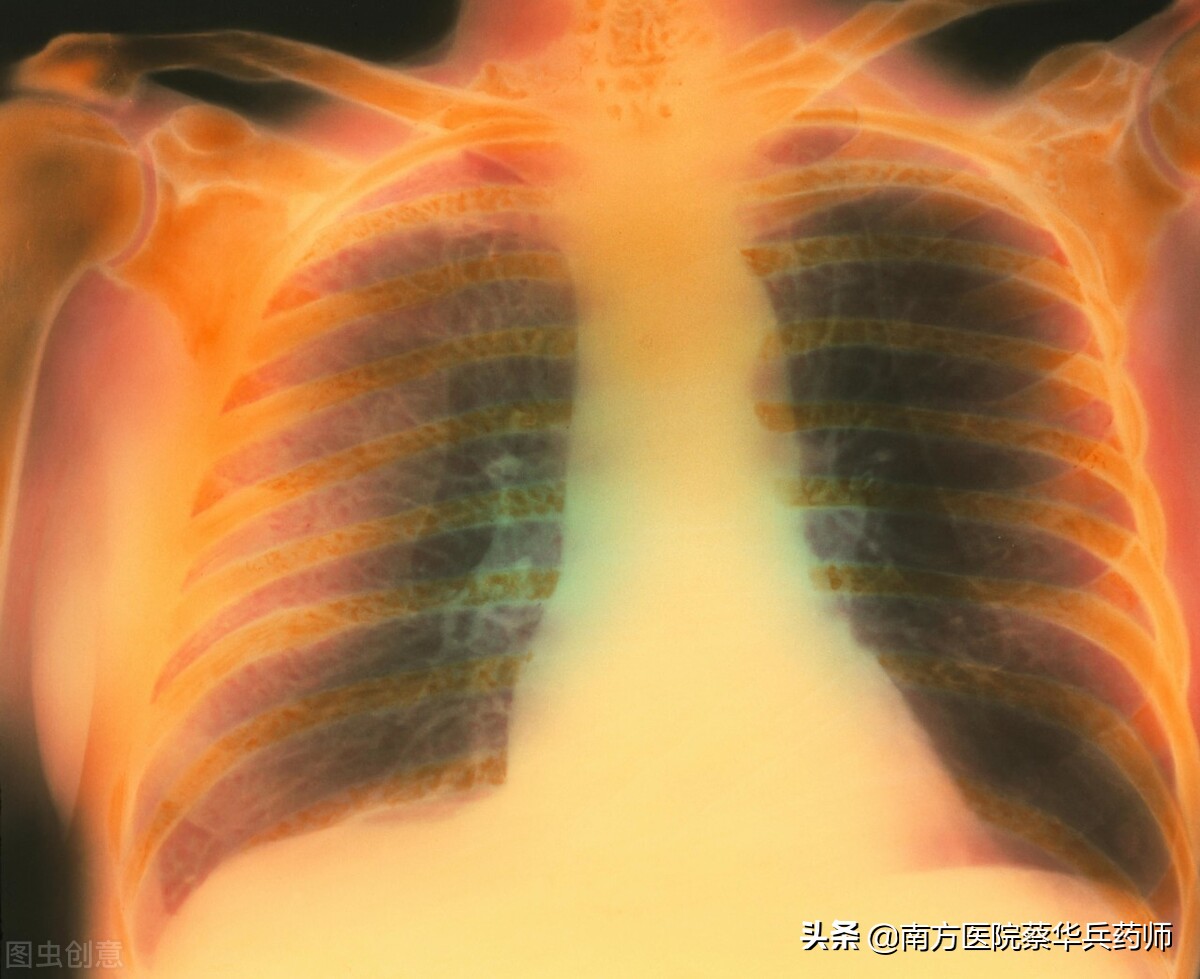

老許是一名67歲的肺氣腫患者,他已經被這討厭的疾病折磨十二年了,並且現在越來越嚴重。每到冬天,他就像走了一趟“鬼門關”。

慢性支氣管炎、肺氣腫屬寒飲而咳痰清稀者可用本方。